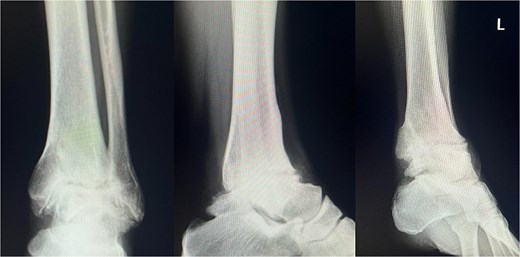

Preoperative radiographs and computed tomography (CT) demonstrated complete loss of the tibiotalar joint space, talar subluxation, and extensive osteophyte formation consistent with end-stage post-traumatic osteoarthritis (Figs 1 and 2). After informed consent and institutional review board approval (IRB number #20251001), the patient underwent arthroscopic ankle arthrodesis.

Preoperative radiological imaging: X-ray finding. The patient presented with end-stage osteoarthritis of the tibiotalar joint, characterized by flattening of the joint surface and subluxation of the talus (↓). Although mild arthritic changes were observed in the subtalar joint (⇓), its articular surface remained preserved.